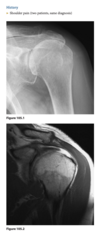

61yr old woman with shoulder pain

AP Radiograph of left shoulder in external and internal rotation (1 & 2) - globular foci of calcification in expected location of supraspinatus (White arrow) and infraspinatus (black arrow) and pectorals major

DIAGNOSIS: Hydroxyapatite deposition disease

(HADD)

HADD consists of crystal deposition in

and around joints, without a known cause.

AKA calcific tendonitis

On radiographs, the calcium deposits appear cloud-

like and amorphous and can involve the tendon,

ligament, bursa, or joint capsule. Intraarticular crys-

tal deposition can destroy the joint space, resulting

in a condition referred to as “Milwaukee shoulder.”

On CT,

­ accompanying erosion of the underlying bone can be

seen. CT appearance has been described as commonly

having a flame-shaped or comet-tail configuration of

the calcifications

If not in shoulder/region not common for HADD ?Malignancy